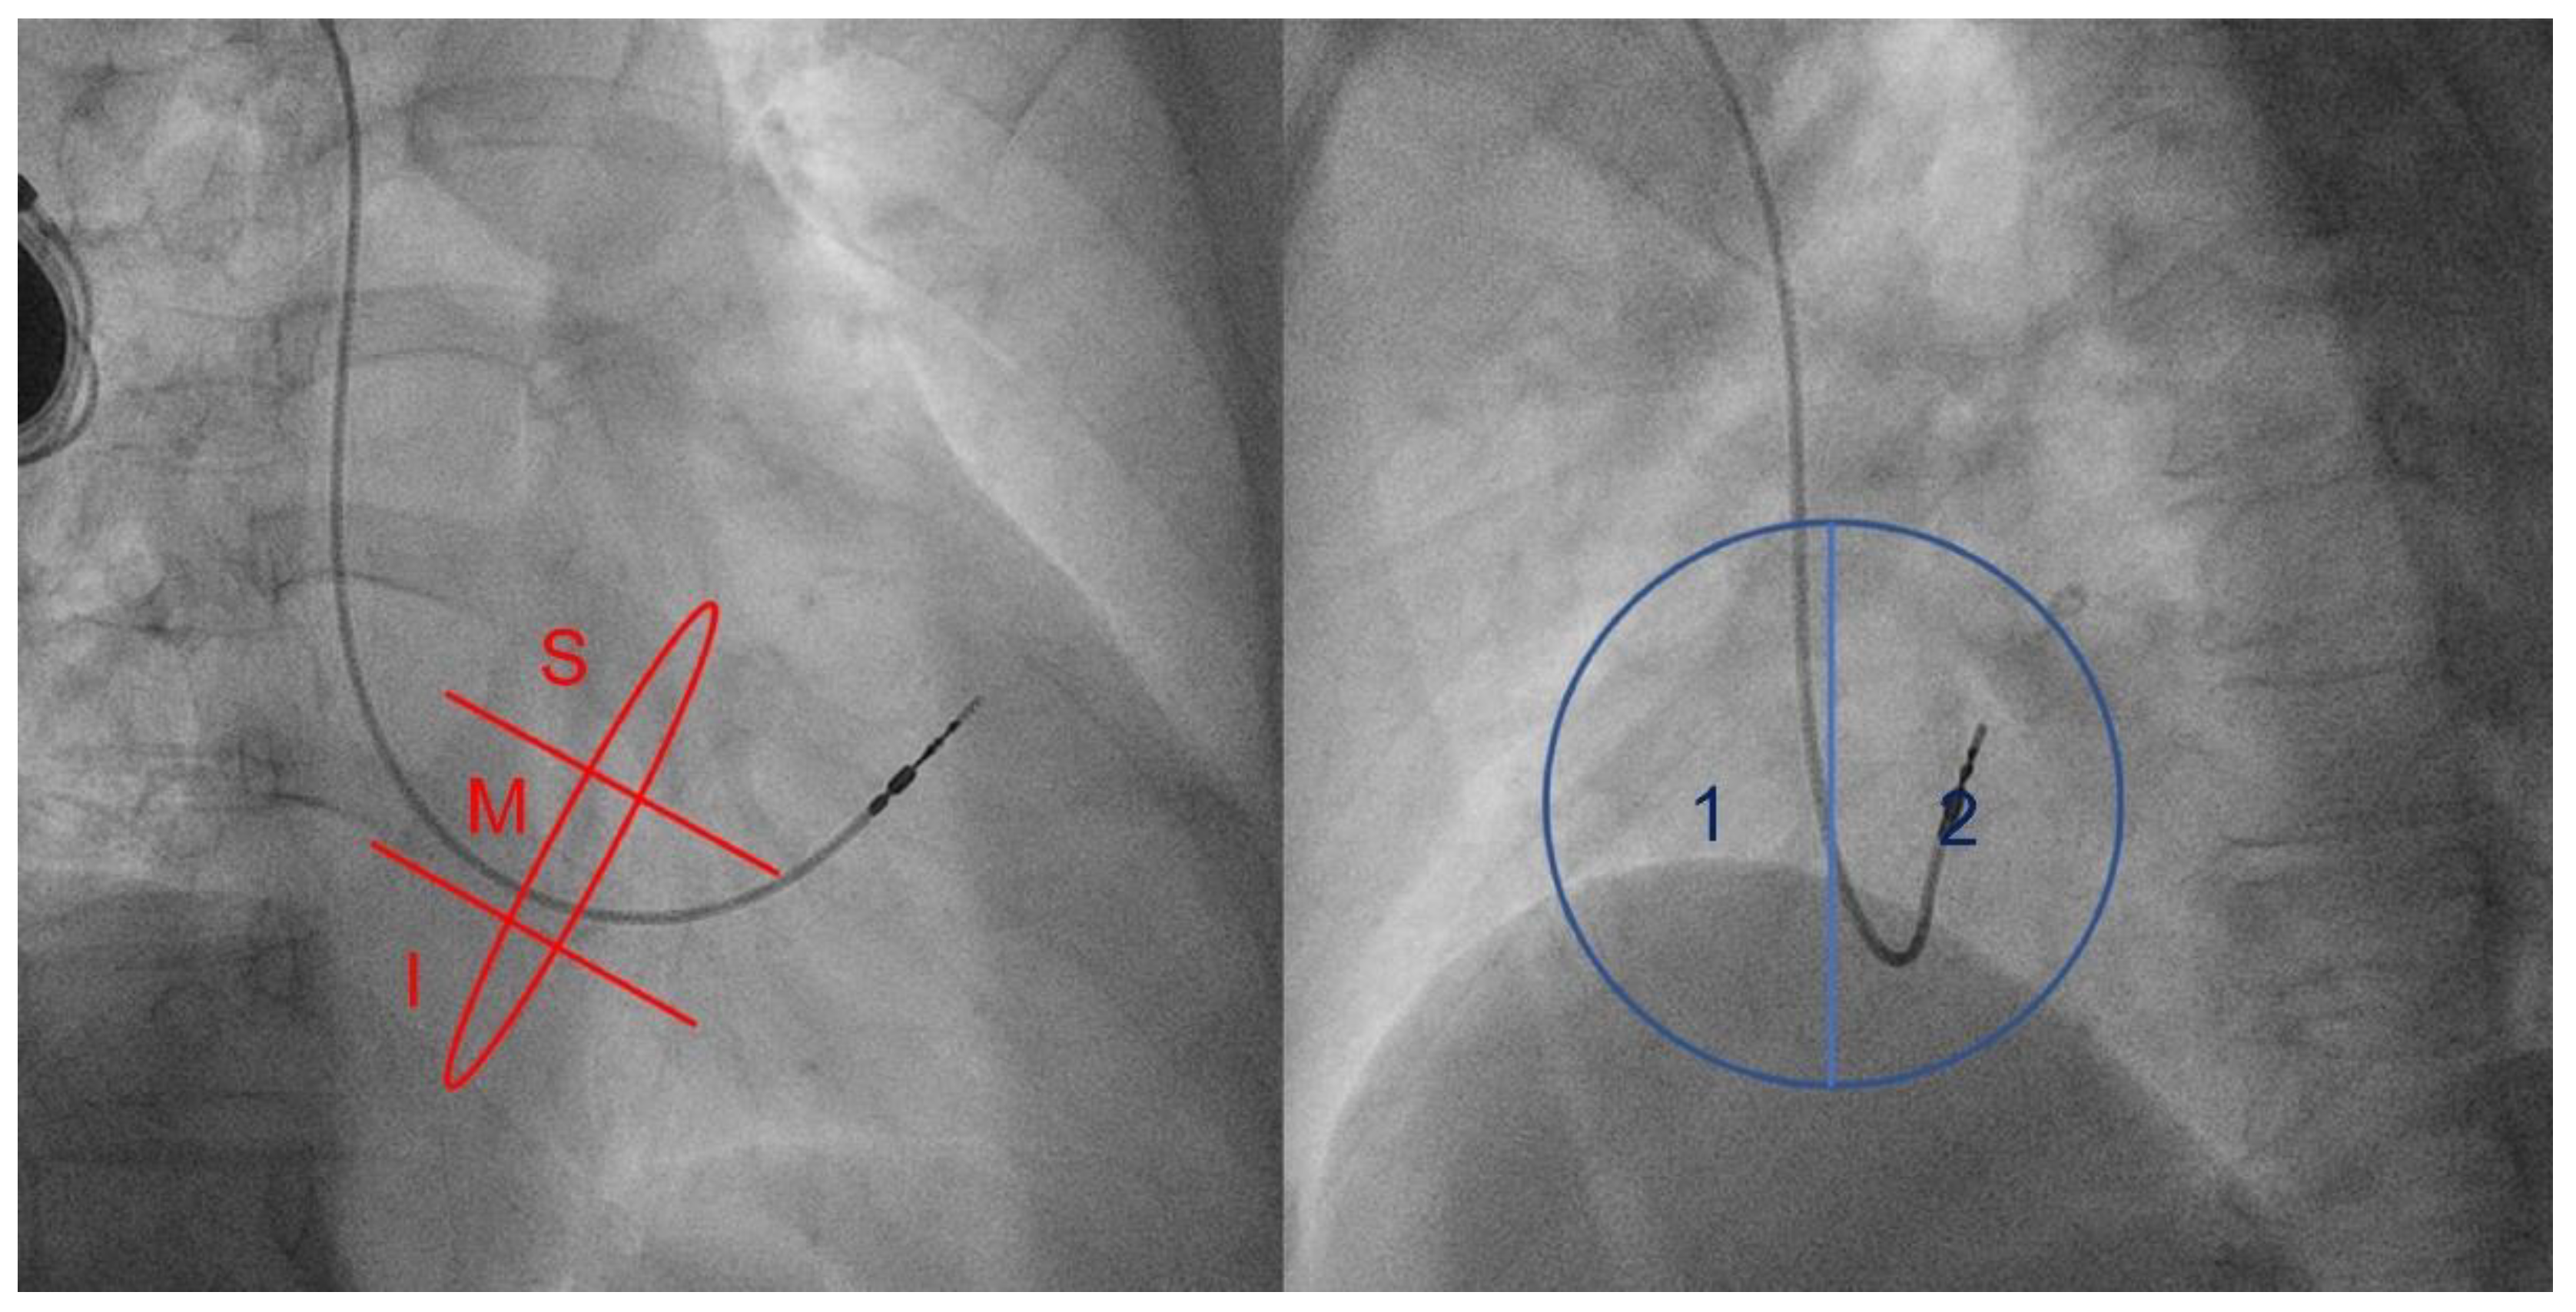

2.1. Fluoroscopy

| RAO, n (%) | ||||

| Mid | 14 (60.9) | 15 (26.3) | 4.36 (1.56–12.13) | 0.04 |

| Inferior | 9 (39.1) | 42 (73.7) | ||

| LAO, n (%) | ||||

| Septal | 21 (91.3) | 41 (71.9) | 4.10 (0.86–19.52) | 0.06 |

| Lateral | 2 (8.7) | 16 (28.1) | ||

| Mid | 16 (76.2) | 13 (22.0) | 11.32 (3.49–36.77) | <0.001 |

| Inferior | 5 (23.8) | 46 (78.0) | ||

| Septal | 19 (90.5) | 43 (72.9) | 3.54 (0.74–16.92) | 0.097 |

| Lateral | 2 (9.5) | 16 (27.1) | ||